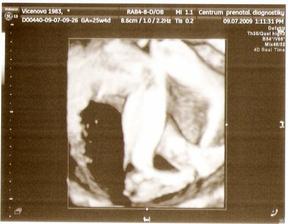

9.7. - 3D UTZ - vše ok, malá měla pořád ručičku před obličejíkem, takže zepředu se nám moc neukázala, ale z profilu ano, má špičatou bradičku :o) a váží 780 g :o)